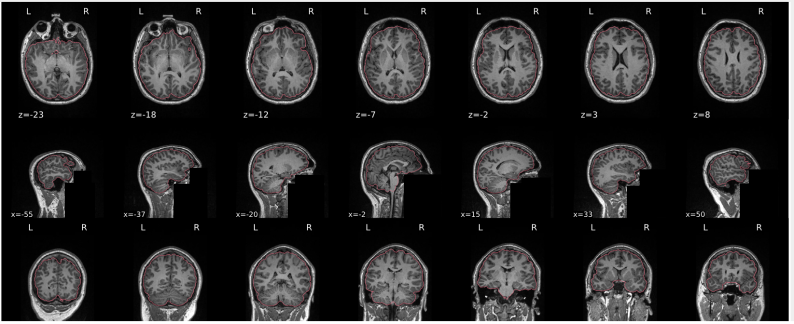

T1w skull stripping

Skull stripping is the process separating the brain (cortex and cerebellum) from the skull. The red line follows the outline of the brain and it separates it from the skull.

Example of a good subject

- There are no skull stripping errors, such as portions of the brain missing, or too much of the skull retained

- The red line follows the outline of the brain

Example of a bad subject

- There are skull stripping errors, such as portions of the brain missing, or too much of the skull retained

- NOTE: check all the images (slices) in the report. If only one image (slice) looks problematic, it is possible that the subject is okay and it is just a visual issue in that particular screenshot

Summary

| Good | Bad |

|---|---|

| The brain is fully inside the red line | Structures like the cranium or the eyes are inside the red line |

| No important brain structures are outside of the red line red line follows the natural outline of the brain | Important brain structures are missing inside of the red line |

-> if only one slice is problematic, it could be an issue related to the visual depiction of the data instead of an issue related to the test subject